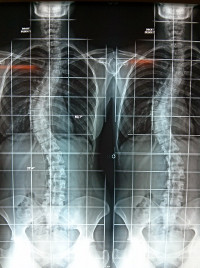

- Shortening osteotomy and sacro-sacral fixation for U-shaped sacral fractures. Sabourin M, Lazennec JY, Catonne Y, Pascal-Moussellard H, Rousseau MA. J Spinal Disord Tech. 2010 Oct;23(7):457-60. doi: 10.1097/BSD.0b013e3181bee88f. PubMed PMID: 20921873.

- Three-dimensional stereoradiographic modeling of rib cage before and after spinal growing rod procedures in early-onset scoliosis Sabourin M, Jolivet E, Miladi L, Wicart P, Rampal V, Skalli W. . Clin Biomech (Bristol, Avon). 2010 May;25(4):284-91. doi: 10.1016/j.clinbiomech.2010.01.007. Epub 2010 Feb 2. PubMed PMID: 20129725.

- Surgical management of pelvic primary bone tumors involving the sacroiliac joint. Sabourin M, Biau D, Babinet A, Dumaine V, Tomeno B, Anract P. Orthop Traumatol Surg Res. 2009 Jun;95(4):284-92. doi: 10.1016/j.otsr.2009.04.008. Epub 2009 May 30. PubMed PMID: 19482533.

- Fractures du Sacrum - Rappels anatomiques et classification. Sabourin M, Rousseau MA, Sofia T, Lazennec JY : In Traumatismes de la ceinture pelvienne. Sauramps Medical. 2007.pp 143-150

- Fractures en U du sacrum - Mécanisme physiopathologique et expérience de la Pitié. Sabourin M, Rousseau MA, Sofia T, Lazennec JY, Bendaya S In Traumatismes de la ceinture pelvienne. Sauramps Medical. 2007. pp 151-160